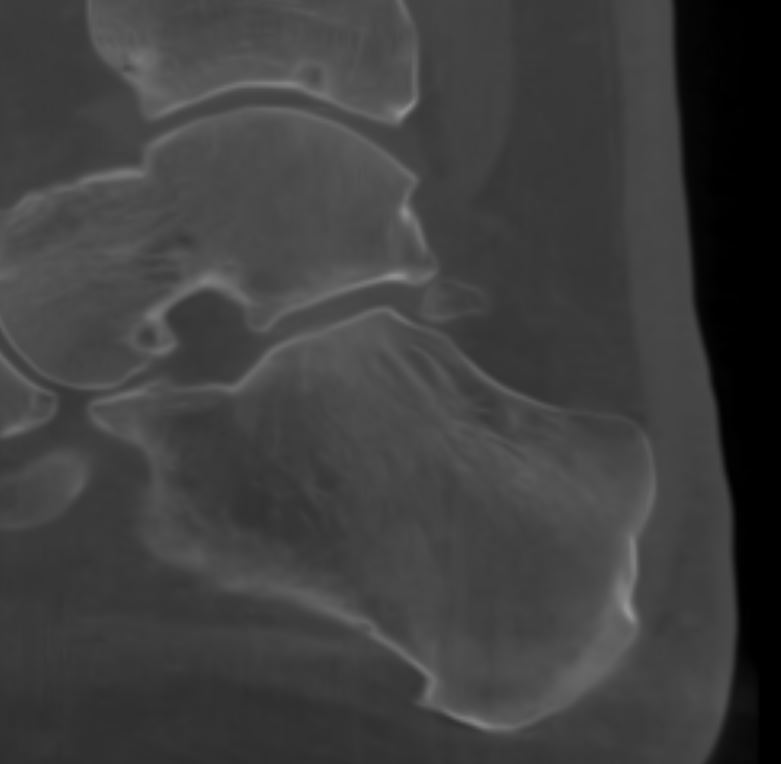

Home Schwerpunkte Krankheitsbilder Os Trigonum Syndrom os trigonum eingeklemmt im USG DVT sagital

os trigonum eingeklemmt im USG DVT sagital

OS trigonum eingeklemmt im USG Gelenkspalt vor der Operation